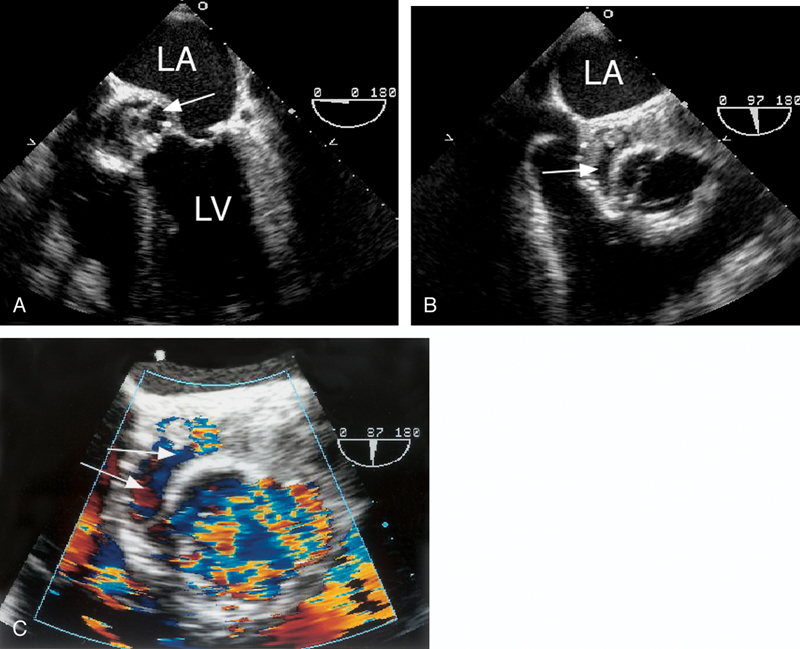

فحوصات تشخيصية لبعض امراض القلب والشرايين التاجية